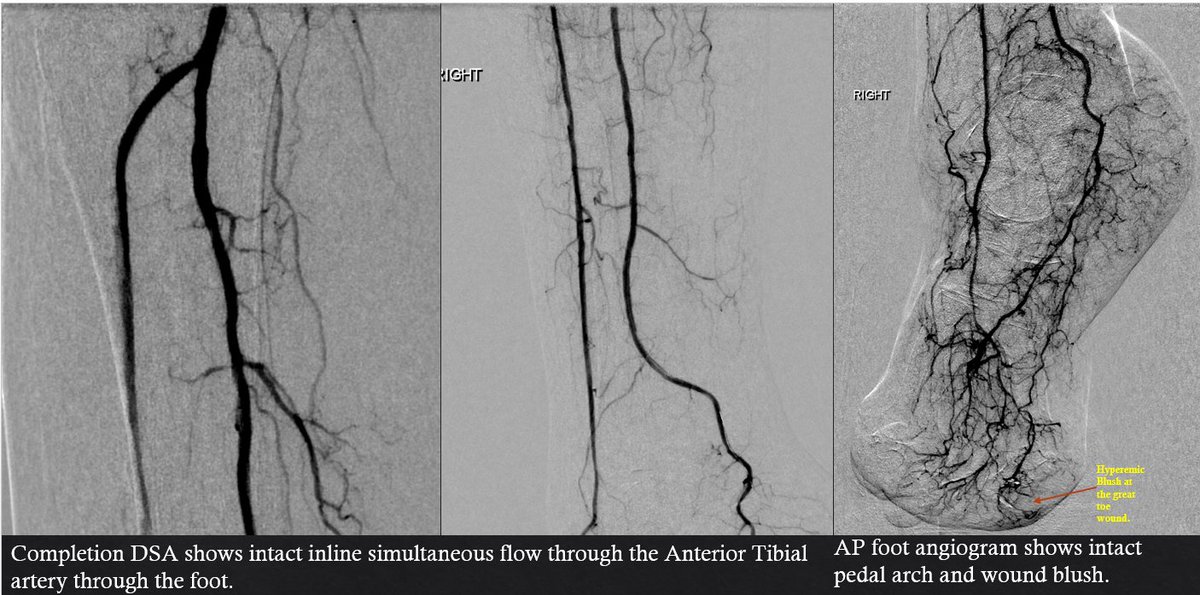

#CLIFighters Non-healing heel and toe ulcer, being offered amputation, after revascularization of PT, plasty AT and peroneal, blush at the wound and bleeding #MyLegMyLife @ZagumBhatti @roblookstein @kmadass @LessneVIR @keithppereira @JVIRmedia @Saukalaka @BostonPIMedEd